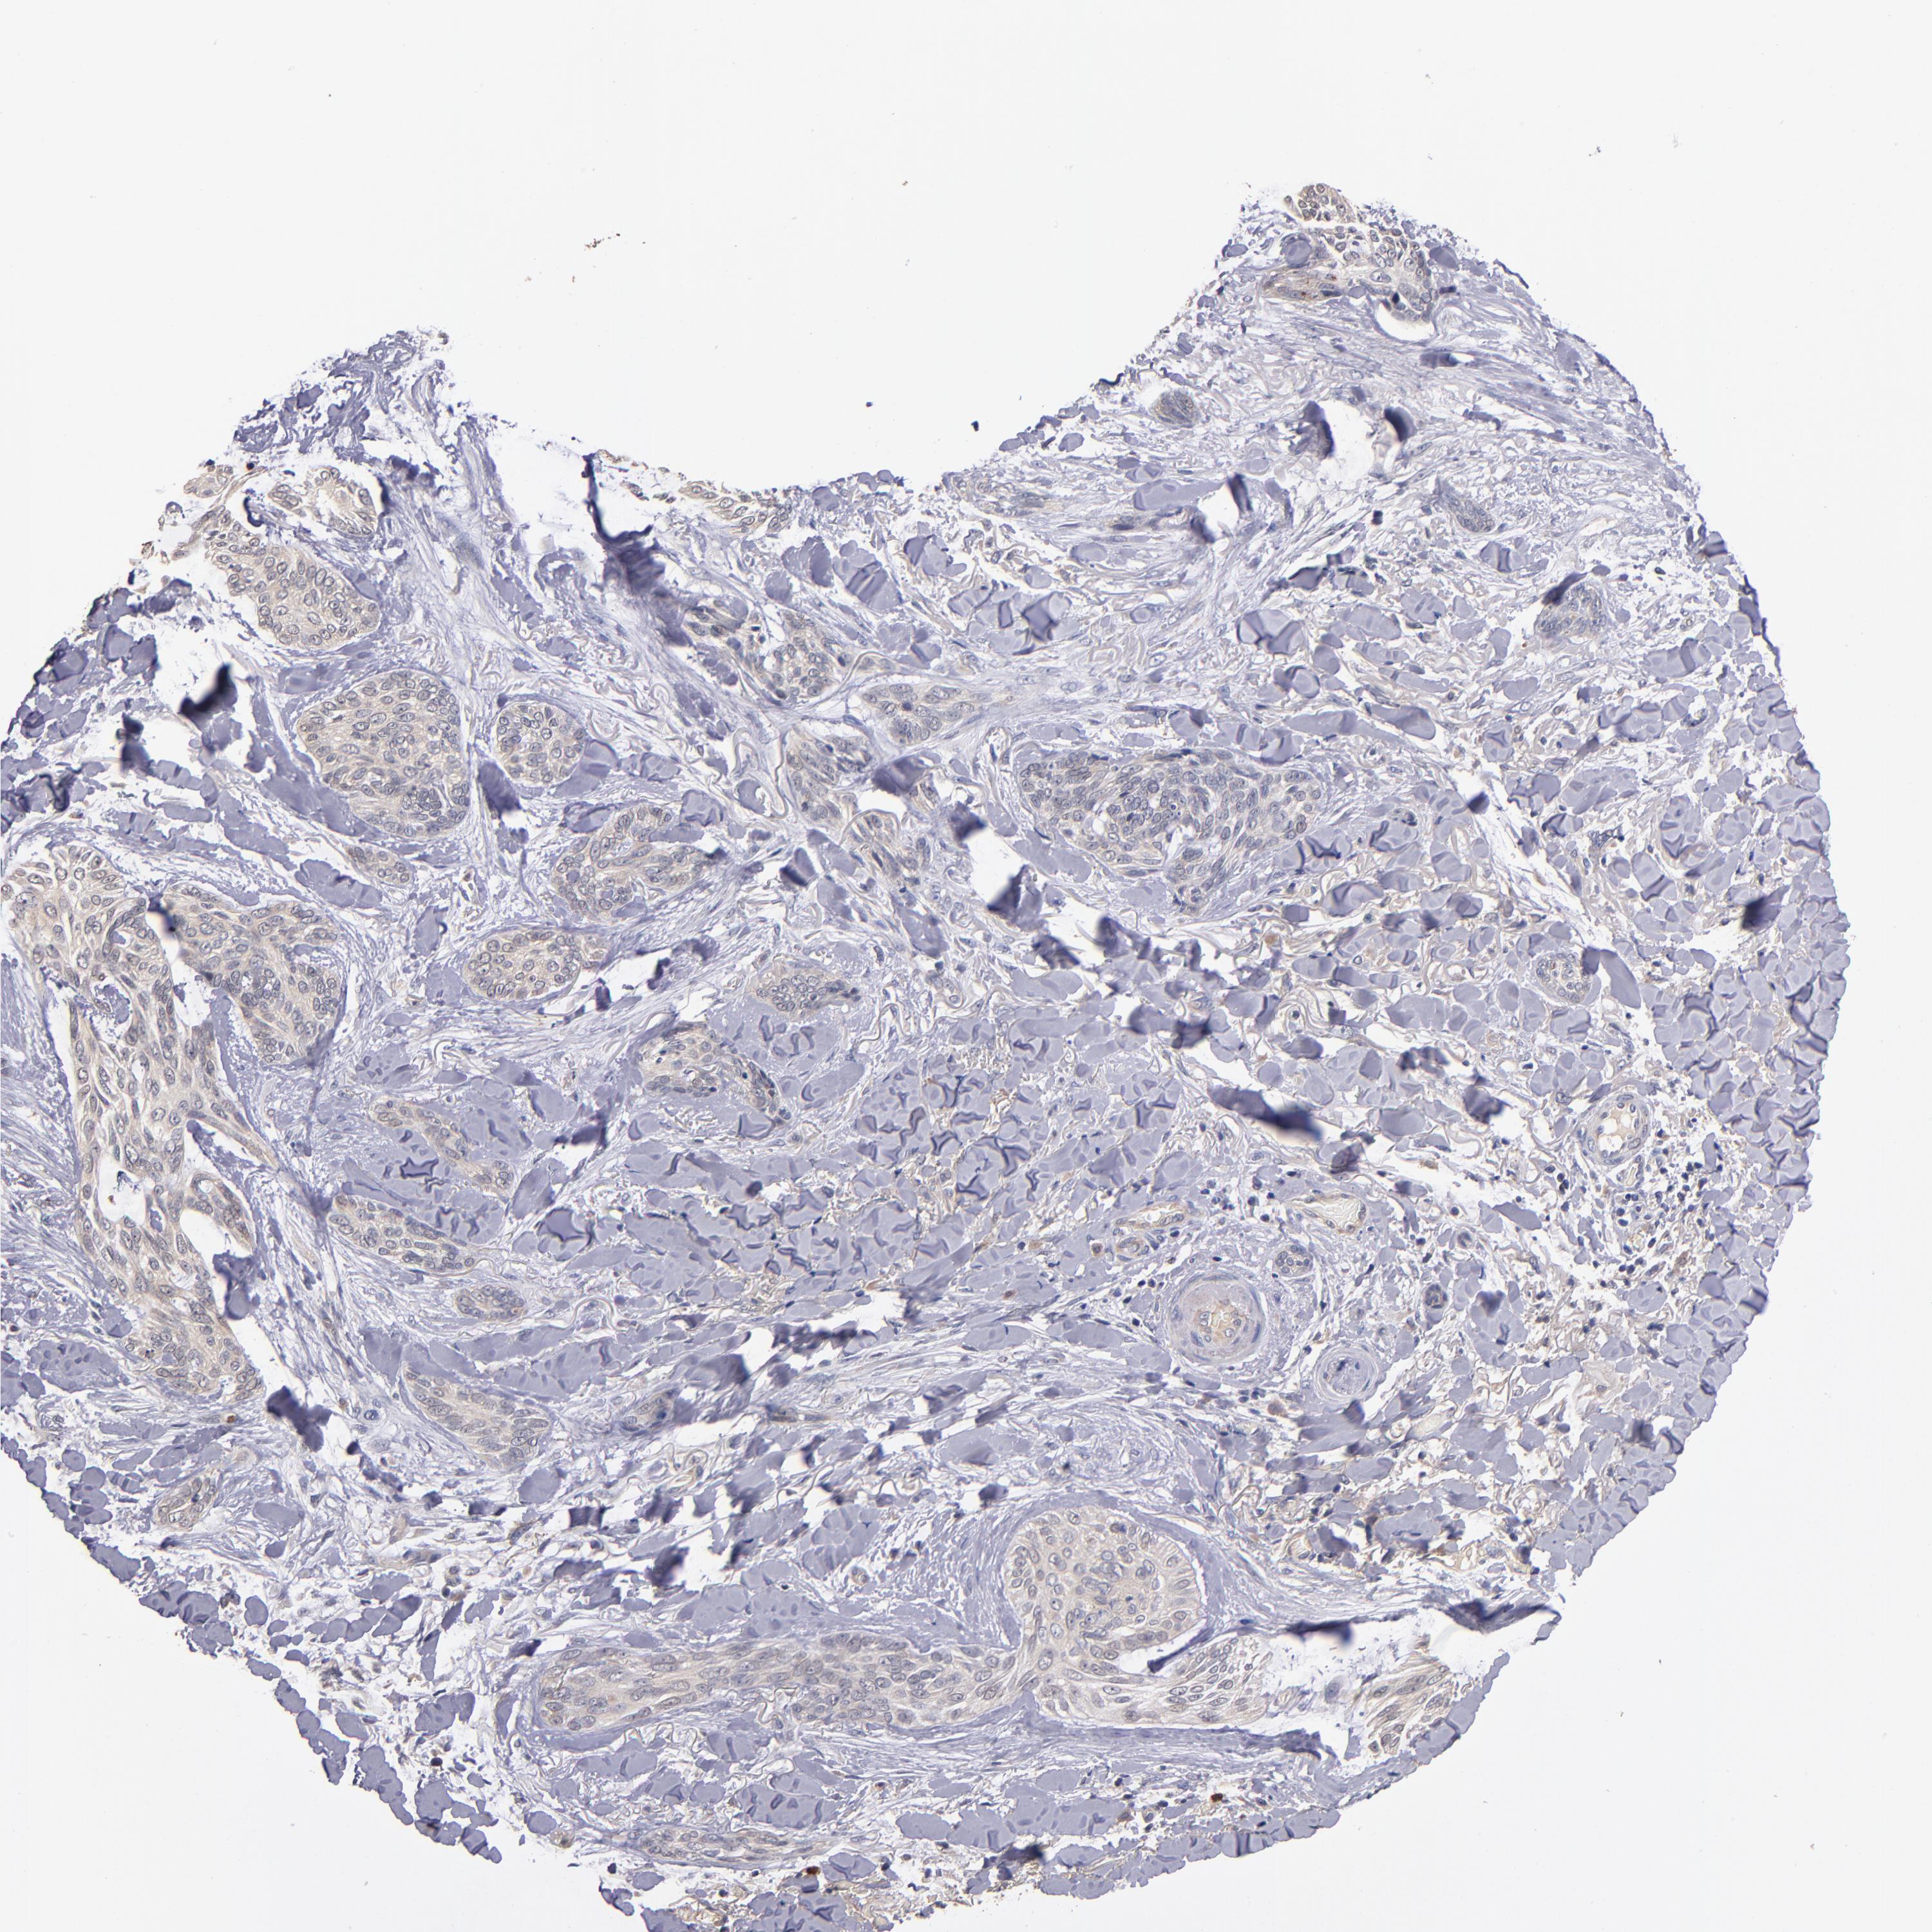

SKIN CANCER - Protein expressioni

A mouse-over function shows sample information and annotation data. Click on an image to view it in a full screen mode. Samples can be filtered based on level of antibody staining by selecting one or several of the following categories: high, medium, low and not detected. The assay and annotation is described here.

Each image is clickable and will lead to virtual microscopy that enables deeper exploration of all samples and also displays staining intensity scores, fraction scores and subcellular localization as well as patient and tissue information for each sample.

Antibody CAB046029

Basal cell carcinoma